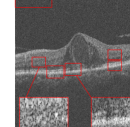

For testing the algorithm for the super-resolution of images of dataset3, 1 subject from each category has been selected and the algorithms have been applied for the super-resolution of artificially missed B-scans. Patch sizes were set equal to 5 and 7 with window size [2,2] and window size for MDT was set to [4,4] (recall that the window size for MDT has been selected for achieving the best output). The results have been presented in Fig. 7. Similar to the dataset2, in this dataset, no reference image is available and only visual comparison and CNR have been reported. CNR for each algorithm has been written beneath the resulting image. Visual comparison in addition to the resulting CNR’s, show the effectiveness of the proposed algorithm.

Original noisy image

Incomplete image

Spline interpolation

MDT [43]

Proposed algorithm

CNR = 1.3654

CNR = 0.2807

CNR=1.9968

CNR=2.0549

CNR=2.7711

CNR=1.493

CNR=0.2835

CNR=2.3996

CNR=2.2534

CNR=3.6184

CNR=1.1753

CNR=0.2446

CNR=1.7957

CNR=1.8335

CNR=2.1343